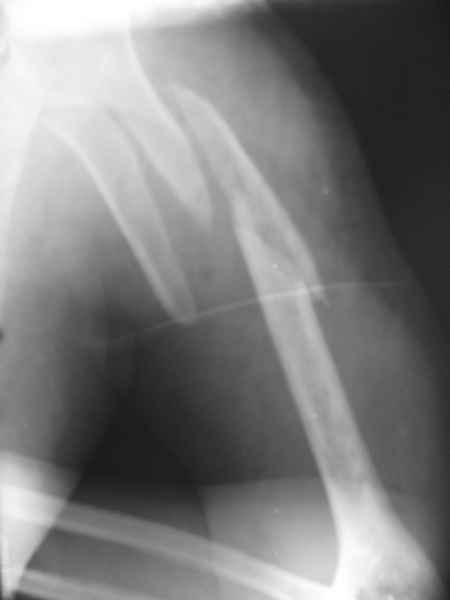

[Ortho] Перелом плеча

Глубокоуважаемые коллеги! Помогите, пожалуйста, определиться с тактикой лечения и оптимальным фиксатором

Травма 20.06, ранее оперативное лечение было невозможно(психоз), перелом закрытый, неосложнённый, обширная гематома.Заранее благодарен.Кирилл